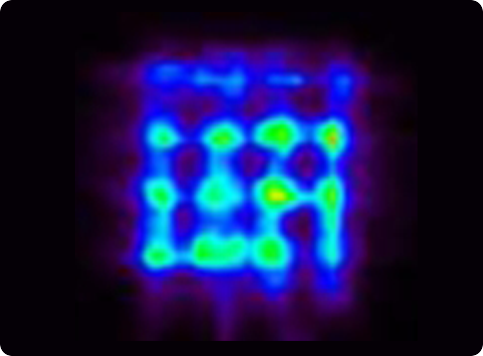

Several crystal-APD units and the corresponding frontend electronics are assembled in detector modules. Our APD-based detector module has 384 LYSO 2x2x20 mm crystals and covers a detection area of ~4x8 cm. One of the advantages the APDs is the capability of performing the double readout of the scintillation crystals, which allows to calculate the DoI of the detected photons. Associated to the fine detector pitch (2x2 mm) and the one-to-one coupling between crystal and APD pixels, the DoI capability permits an excellent spatial resolution of the order of 1.3 mm over the whole Filed-of-View.

Clear-PEM double readout scheme allows calculation of photon Depth of Interaction (DOI) and compensates blurring due to the parallax effect in PET resulting in an isotropic image resolution of 1.3 mm FWHM.

Due to its very good spatial resolution and accessibility of the Field-of-View, the Clear-PEM system can also be used for small animal imaging.